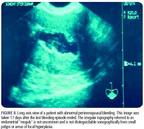

In that study, 280 patients (65%) displayed a thin, distinct, symmetric endometrial echo of 5 mm or less on day 4 through 6, and dysfunctional uterine bleeding was diagnosed (Figure 2). One hundred fifty-three (35%) had SIS. Of these procedures, 44 (29%) were performed because of the inability to adequately characterize and measure the endometrium (Figures 3 and 4) and 109 (71%) were done for endometrial measurement of 5 mm or more. Sixty-one of those patients then had both anterior and posterior endometrial thickness that was symmetric and less than 3 mm, compatible with dysfunctional uterine bleeding. Of the original 433 patients in the study, 58 patients (13%) had focal polypoid masses (Figure 5) that were removed hysteroscopically and confirmed pathologically. Twenty-two patients (5%) had submucous myomas although 148 patients (34%) had clinical and ultrasonographic evidence of fibroids. Ten patients had single-layer measurements of endometrium of more than 3 mm (range 39 mm) during SIS. Of these, five patients had a proliferative endometrium and five had a hyperplastic endometrium. SIS was technically inadequate in two patients, who then underwent hysteroscopy with curettage. Undirected office biopsy alone without imaging would have potentially missed the diagnosis of focal lesions such as polyps, submucous myomas, and focal hyperplasia in up to 80 patients (18%).